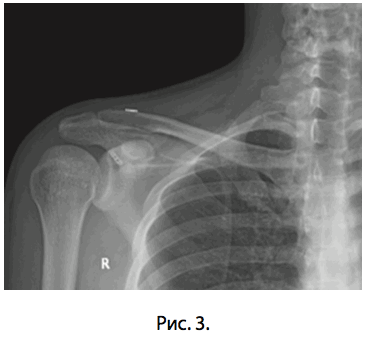

Ранний послеоперационный период протекал без осложнений, рана зажила первичным натяжением, швы удалены в положенные сроки. Больной соблюдал предписанный ему режим иммобилизации ортезом типа Дезо. По прошествии 4-х недель с момента операции произведено удаление спиц и выполнена контрольная ренгенография (рис. 3).